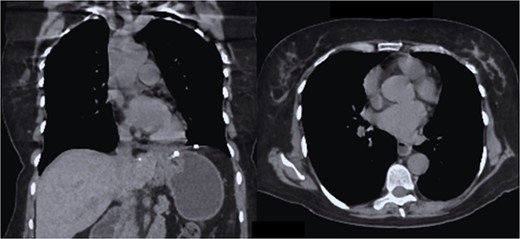

The case is reported of a 52-year-old woman, without significant illnesses, who presented with non-specific chest pain for 1 year, 6 months later with intermittent episodes of dyspnea with great and medium exertion, dysphagia, and heartburn. During the examination, hypoventilated lung fields at the bases, peristaltic sounds, and tympanism on percussion were heard. The thoracoabdominal tomography with contrast shows a diaphragmatic hernia containing the stomach, portions of the duodenum, pancreas, small intestine, and colon (Fig. 1), with a sac measuring up to 20 cm (Fig. 2).

CT coronal section, showing the presence of the stomach, duodenum, small intestine, colon, and pancreas.